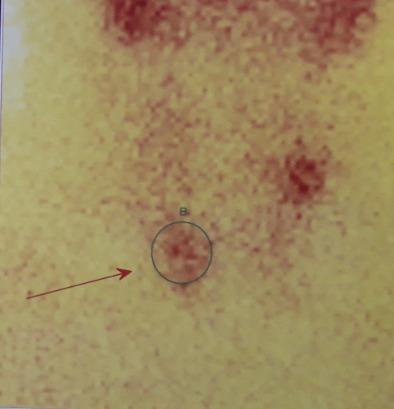

Multiple endocrine neoplasia type 1 (MEN1) is a rare disease, defined as a tumor developing in at least two endocrine glands including the anterior pituitary gland, the parathyroid glands and the duodenopancreatic endocrine tissue. This disorder, inherited in an autosomal dominant pattern, is caused by mutations in the MEN1 gene encoding the tumor suppressor menin and located on chromosome 11q13. However, sporadic cases account for 8-14%. The first endocrine lesion may be solitary in approximately 75% of cases. However, all major alterations can be inaugural. We here report a case of multiple endocrine neoplasia type 1 revealed by aggressive somatoprolactinic pituitary adenoma which didn't respond to conventional treatment. The detection of primary hyperparathyroidism as well as neuroendocrine tumor of the pancreas seven years later make this a very particular case. Therapeutic options are discussed within the multidisciplinary team specialized in endocrine diseases.

多发性内分泌腺瘤1型(MEN1)是一种罕见疾病,定义为在至少两个内分泌腺发生肿瘤,这些内分泌腺包括垂体前叶、甲状旁腺和十二指肠胰腺内分泌组织。这种疾病以常染色体显性模式遗传,由位于11q13染色体上编码肿瘤抑制因子menin的MEN1基因突变引起。然而,散发病例占8 - 14%。在大约75%的病例中,首个内分泌病变可能是孤立性的。然而,所有主要病变都可能是首发的。我们在此报告一例由侵袭性生长激素泌乳素型垂体腺瘤引发的多发性内分泌腺瘤1型病例,该垂体腺瘤对传统治疗无反应。七年后检测出原发性甲状旁腺功能亢进以及胰腺神经内分泌肿瘤,使该病例非常特殊。在专门从事内分泌疾病的多学科团队中讨论了治疗方案。